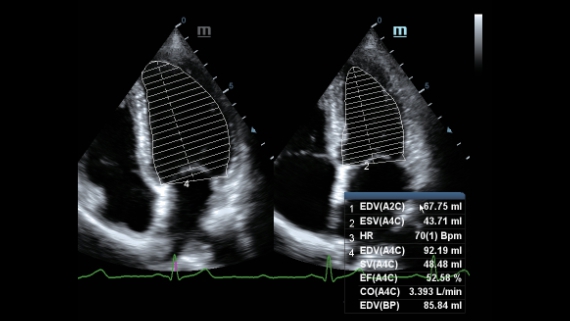

X-Insight ├© una soluzione completa studiata per offrire la migliore qualit├Ā diagnostica.

Progettato per rispondere al meglio alle esigenze del cliente, DC-60 Exp con X-Insight ├© studiato per offrire un'efficienza elevata nel campo dell'imaging di precisione, grazie a una chiarezza immediata (eXpress Clarity), allŌĆÖeccezionale intelligenza (eXceptional Intelligence), oltre a vantare una lunghissima esperienza (eXceeding Experience).